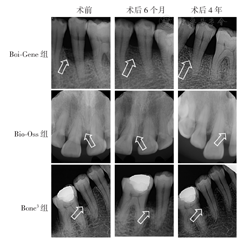

如表2所示,术后6个月、4年,3组患者的RBH%较术前均明显升高(均P<0.05),其变化组间比较差异均无统计学意义(均P>0.05);术后6个月~4年,RBH%变化组间比较差异均无统计学意义(均P>0.05)。图1显示,术后6个月、4年,3组患者骨缺损区均可见新骨形成,且可在4年时维持稳定。

箭头指示纳入研究骨缺损区域